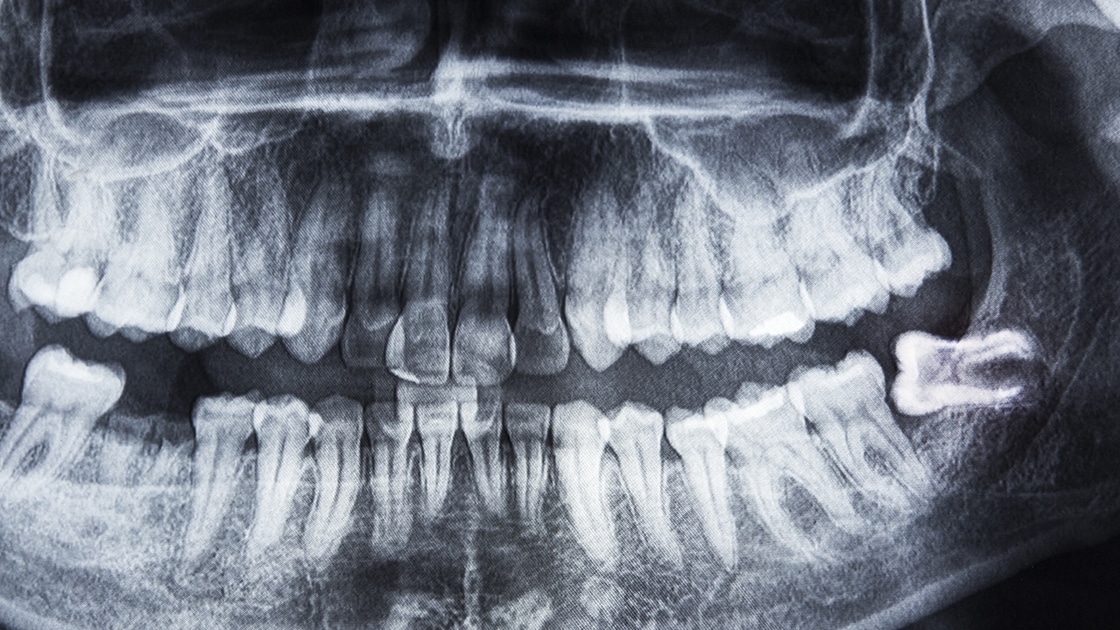

Panorex X-ray

Impacted Tooth & Tooth Exposure

An impacted tooth is a tooth that fails to fully pass through the gums.

Impacted wisdom and cuspid (or canine) teeth are fairly common. To correct impacted teeth, there are a few treatment options. For impacted wisdom teeth, the most common procedure is extraction. For impacted canine teeth, several treatment modalities are available. Orthodontics (braces) can be used to open space for proper eruption. Primary (baby) teeth can either be extracted or surgically exposed to allow for the placement of an orthodontic bracket to help align the teeth.